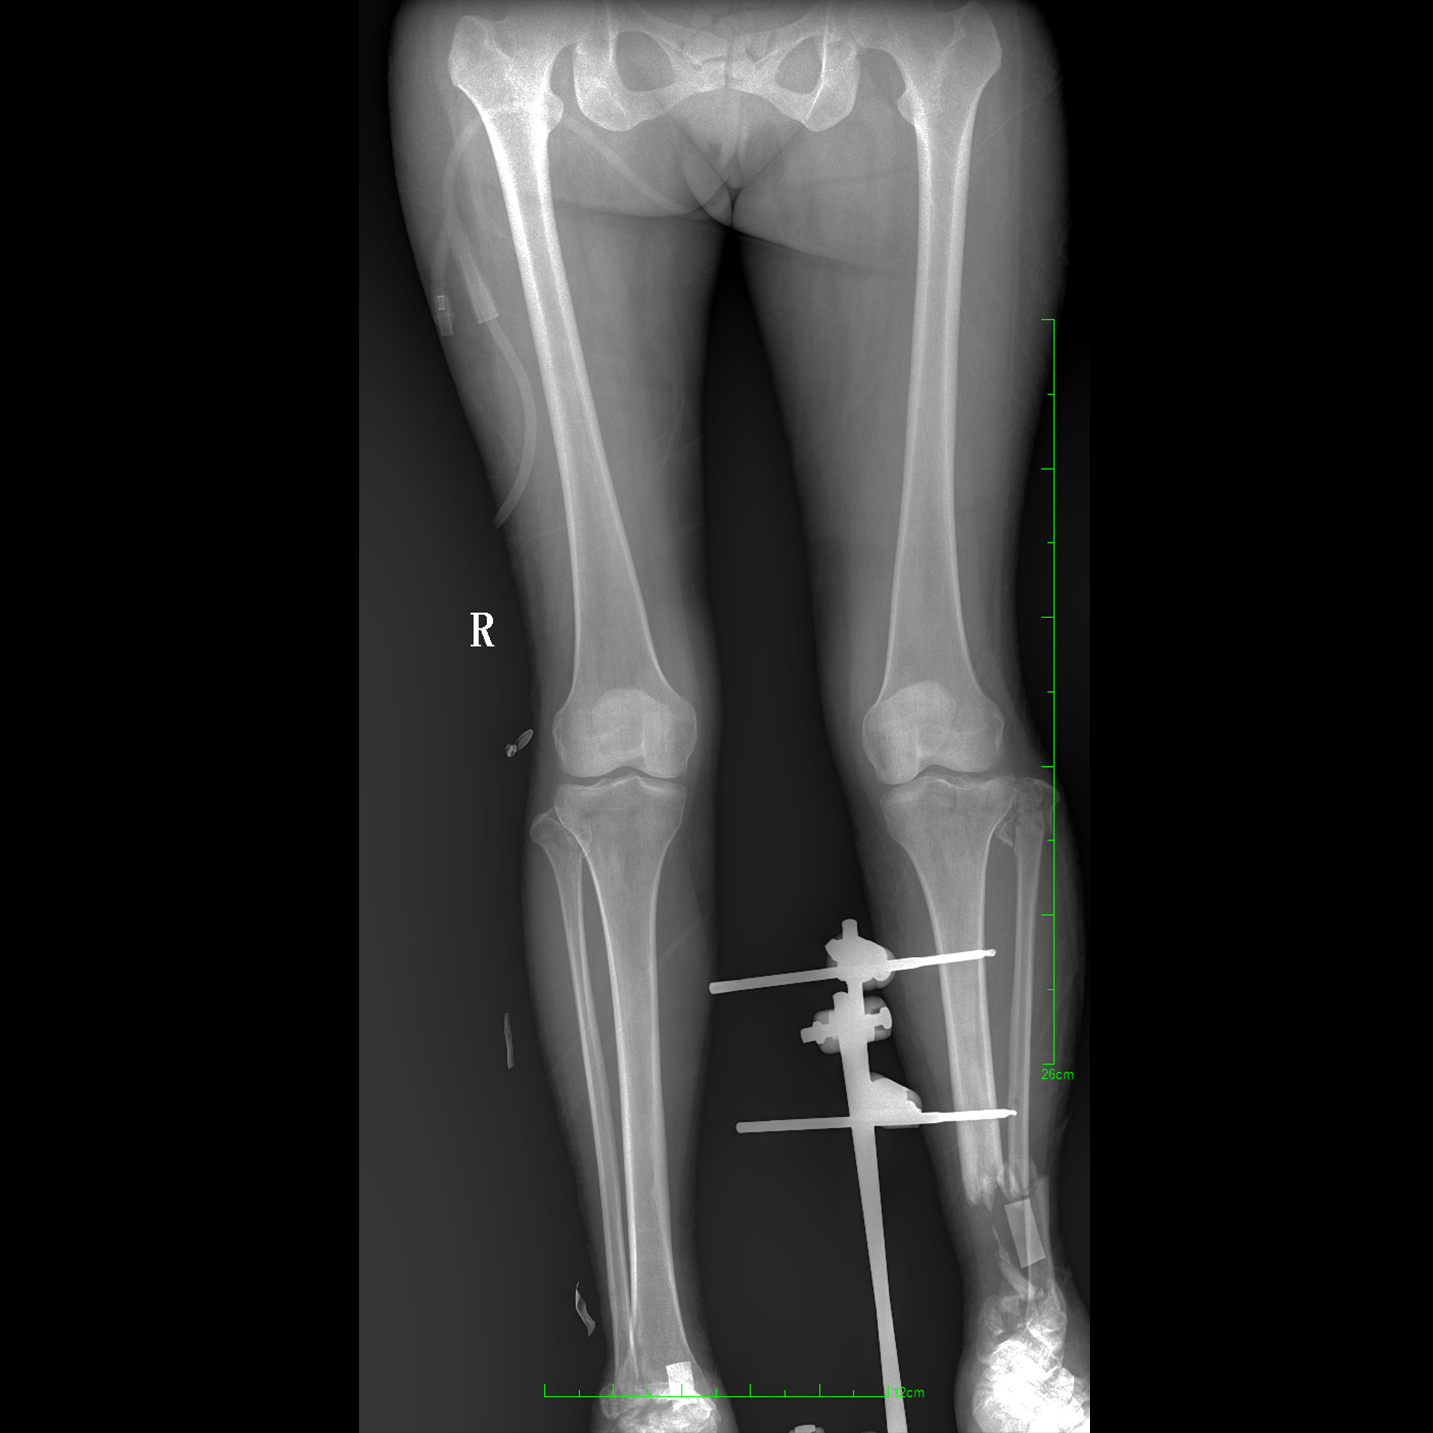

17"*34"有效視野,一次成像不拼接。相較于多張攝影再軟件拼接的DR設備,PLX8600解決了拼接圖像存在密度不均勻,拼接處圖像配準和放大效應等問題,給臨床帶來了大視野影像解決方案,可一次性覆蓋全脊柱或雙下肢影像。